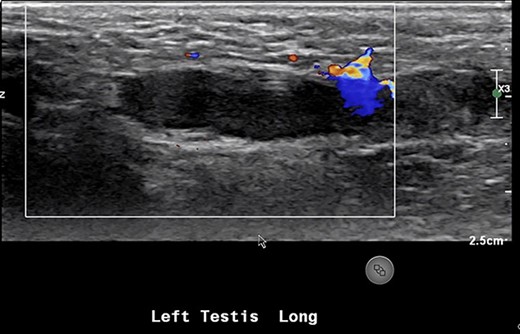

An 18-month-old boy presented to the emergency room with scrotal pain and scrotal discoloration present for 3 hours prior to ED presentation. His parents denied any malodorous or discoloration of his urine. The child was born at term, and immunizations were up to date. On examination, there was no obvious torsion, and testicles were normal lie. He had a scrotal ultrasound showing reduced blood flow in the left testicle, left epididymitis and torsion could not be completely excluded (Fig. 5). He underwent scrotal exploration with findings of normal left testicular lie with no evidence of torsion of the spermatic cord and the epididymis is within normal limits; however, a small hernia containing healthy omentum was identified. The hernia was reduced and repaired with 3-0 vicryl suture.

The majority of indirect inguinal hernias are congenital and are the result of a patent processus vaginalis into which the abdominal viscera can herniate. In Case 1, our patient had an incarcerated hernia with incarcerated omentum. Our patient presented with 1-week history of dull right testicular pain, which could indicate the beginning of vascular compromise to the right testicle. His son had also kicked him in the scrotum prompting him to present acutely. His ultrasound showed he had a complicated large hydrocele and poor blood flow. Testicular infarction due to an incarcerated inguinal hernia in adults is an extremely rare event; there have only been three cases documented in literature [1–3]. In Case 2, a 2-year-old male who also had a left inguinal hernia containing omentum which resulted in reduced blood flow to his left testicle as confirmed on US scrotum. Incarcerated/strangulated omentum in a hernia causing acute scrotum in non-infant pediatric population is an extremely rare event [1, 3, 4], and as in our case often not noticed until surgical exploration.